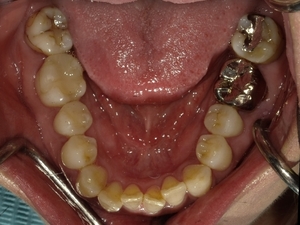

〇ご相談内容:上の前歯が内側に入っている、下の歯のがたつきが気になる〇矯正の種類:マウスピース型矯正「インビザライン」〇治療期間:14週間(約3ヵ月)〇治療費用:44万円(税込)